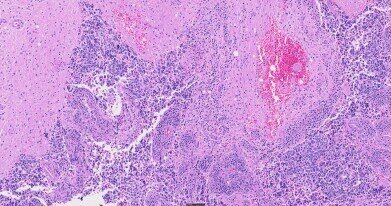

H&E stained tissue, 40X.

The SLIDEVIEW DX VS200 delivers high-resolution, high-throughput scanning for a wide range of pathology applications. Designed for clinical workflows, it supports multiple slide types, magnifications, and imaging modes, ensuring exceptional image quality, reliability, and ease of use.